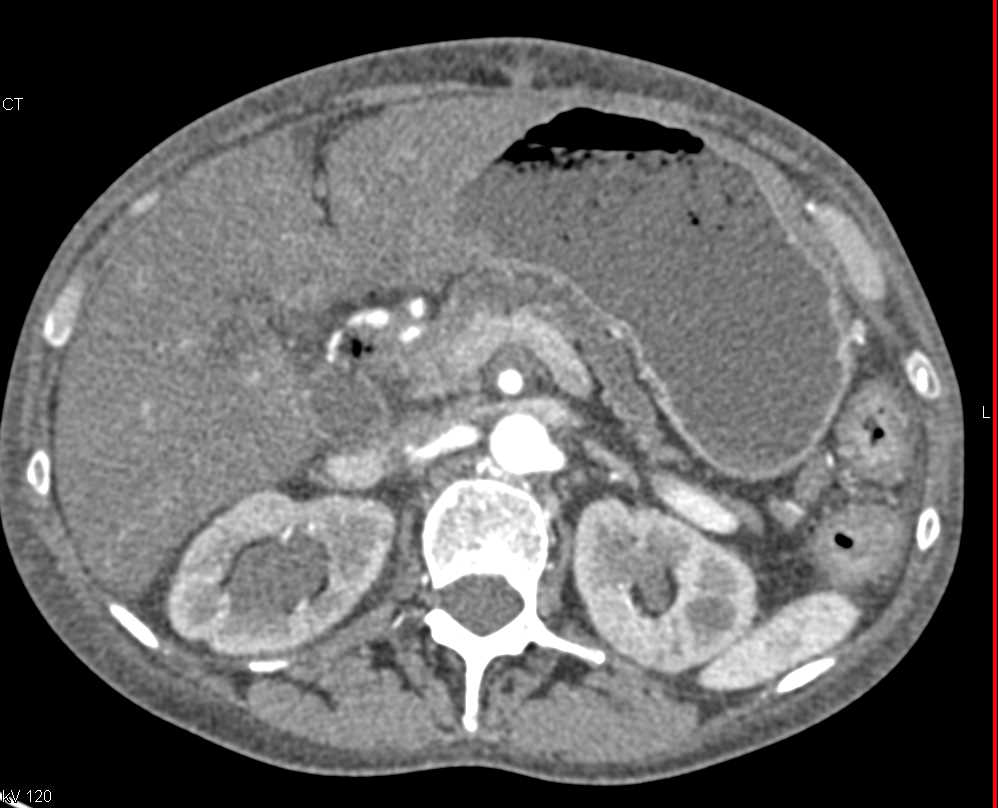

Acute Pancreatitis with Periglandular Necrosis